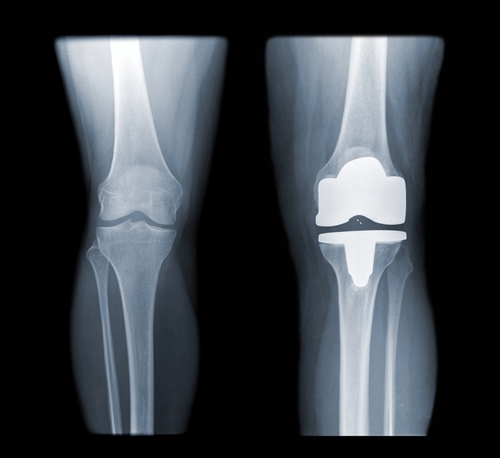

- زانوی ارتو پدیک

تقریبا بسته به محل مورد نظر که برای درمان مد نظر است می توان از سرامیک ها استفاده کرد، به عنوان مثال از سرامیک به عنوان ایمپلنت در موارد زیر استفاده می شود: